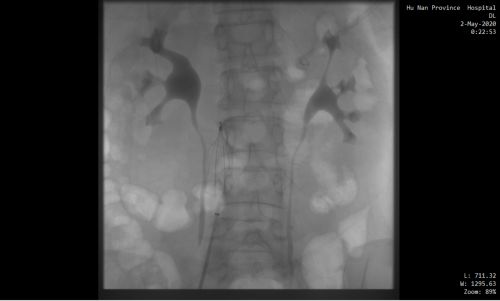

下腔静脉滤器植入后。

情况十万火急,尹新民主任边现场组织抢救,边将情况汇报给向华副院长,向华副院长立即调度全院各相关科室予以协助。一场与生命的赛跑由此拉开!超声科紧急为患者进行床旁彩超,找到肺动脉栓塞的“罪魁祸首”为左下肢静脉血栓。在呼吸治疗组的协助下,医护人员携带转运呼吸机快速运送方女士至介入手术室。介入血管外科紧急安排了手术医生和手术间,由张永琎副主任医师等为患者施行“肺部血管造影”,明确诊断为双肺动脉急性栓塞,随即为其实施“双肺动脉尿激酶冲击溶栓、下腔静脉滤器植入术”。术后,患者肺动脉供血明显改善,血氧饱和度立即回升,被送往重症医学一科继续治疗。